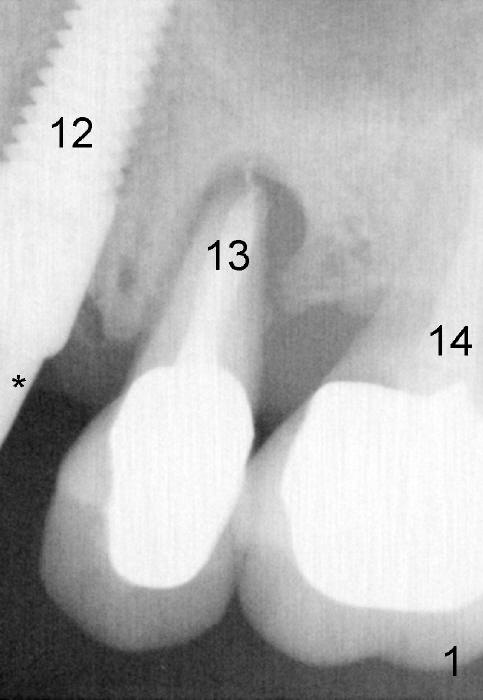

As soon as the tooth #12 is extracted and replaced with immediate implant, the patient feels that pain shifts to the tooth #13 (Fig.1 taken 3 months post implantation of #12; *: abutment).  By the 7th months postop (Fig.2 C: crown), the patient agrees to have a 2nd implant for the tooth #13.  Thorough debridement of the socket is planned.  Sinus lift is expected.  Take preop PA and photos.